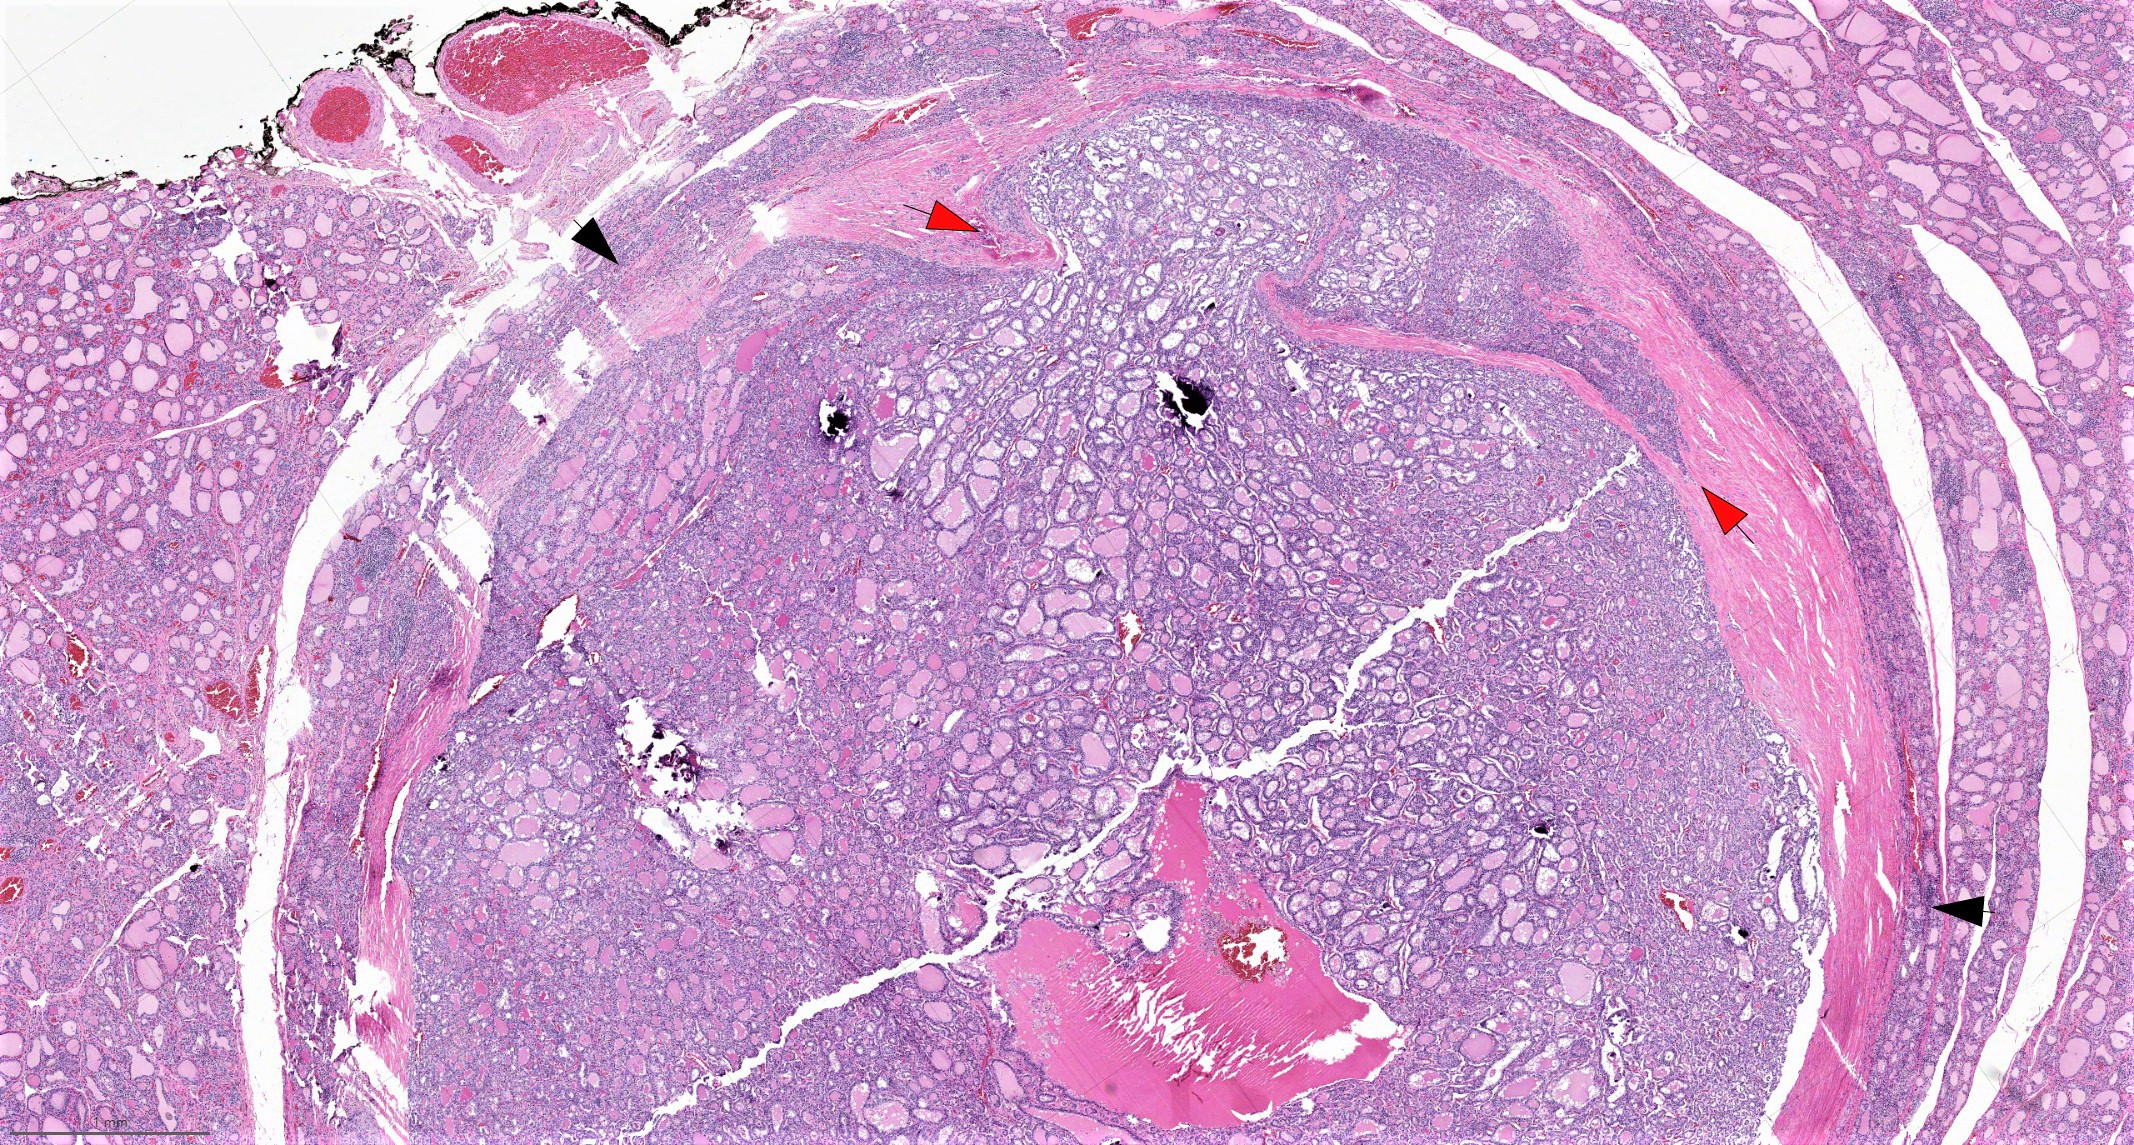

Microscopic (histologic) description

- Architecture: exclusively or nearly exclusively follicular

- Encapsulated follicular variant has a complete fibrous tumor capsule or a well circumscribed tumor border

- Infiltrative follicular variant shows infiltrative or multinodular growth

Microscopic (histologic) images